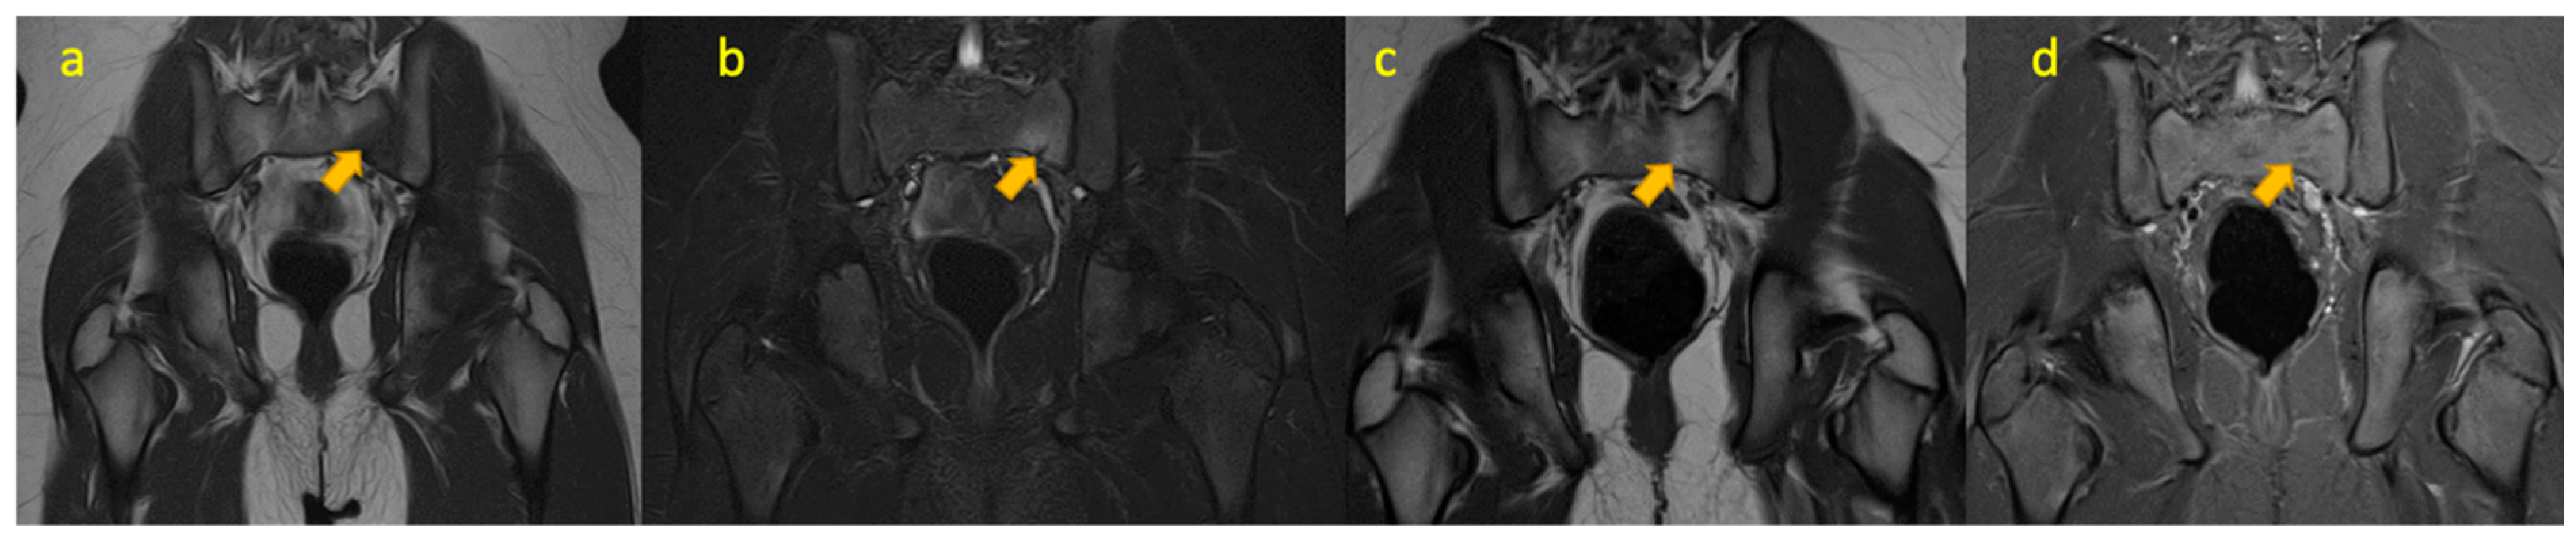

5. Juvenile Idiopathic Arthritis of the Hip

6. Rectus Femoris Avulsion Fracture

7. Crystal Arthritis of the Hip

8. Osteomyelitis Iliac Crest